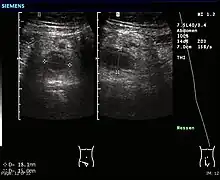

Ultrasound

Abdominal ultrasonography, preferably with doppler sonography, is useful to detect appendicitis, especially in children. Ultrasound can show the free fluid collection in the right iliac fossa, along with a visible appendix with increased blood flow when using color Doppler, and noncompressibility of the appendix, as it is essentially walled-off abscess. Other secondary sonographic signs of acute appendicitis include the presence of echogenic mesenteric fat surrounding the appendix and the acoustic shadowing of an appendicolith.[45] In some cases (approximately 5%),[46] ultrasonography of the iliac fossa does not reveal any abnormalities despite the presence of appendicitis. This false-negative finding is especially true of early appendicitis before the appendix has become significantly distended. Also, false-negative findings are more common in adults where larger amounts of fat and bowel gas make visualizing the appendix technically difficult. Despite these limitations, sonographic imaging with experienced hands can often distinguish between appendicitis and other diseases with similar symptoms. Some of these conditions include inflammation of lymph nodes near the appendix or pain originating from other pelvic organs such as the ovaries or Fallopian tubes. Ultrasounds may be either done by the radiology department or by the emergency physician.[47]

-

Ultrasound showing appendicitis and an appendicolith[48]

Ultrasound showing appendicitis and an appendicolith[48] -

Ultrasound of a normal appendix for comparison -

A normal appendix without and with compression. Absence of compressibility indicates appendicitis.[45]